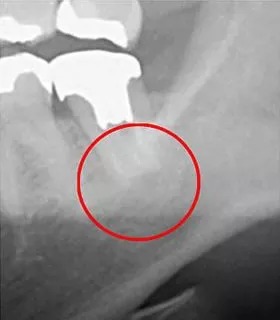

次の写真はCTとレントゲンで撮影した虫歯の画像を比較したものです。

「左」がCTで撮影した画像、「右」が一般的に利用されているレントゲンで撮影した画像です。丸がついている部分が問題の生じている部分です。

一般のレントゲンでは白く何も映っていませんが、CTでは黒い影が確認できます。